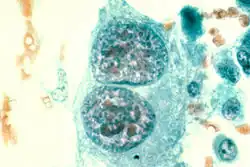

Kostniakomięsak drobnokomórkowy

Jest to podtyp histopatologiczny kostniakomięsaka zbudowany z małych komórek nowotworowych w różnym stopniu produkujący osteiod. Stanowi około 1,5% przypadków kostniakomięsaka u ludzi[56]. Makroskopowo nowotwór jest podobny do kostniakomięsaka klasycznego. Mikroskopowo budują go małe komórki, które mogą przybierać okrągły lub wrzecionowaty kształt[56]. Komórki mogą przypominać mięsaka Ewinga lub chłoniaka[56][57]. Komórki okrągłego kształtu mogą osiągać bardzo niewielkie rozmiary, zawierają niewielką ilość cytoplazmy, jądro jest okrągłe lub owalne. Komórki wrzecionowate cechują się krótkimi wrzecionowatymi jądrami, choć te mogą przyjmować okrągły kształt. W nowotworze zawsze stwierdza się obecność osteoidu[56].